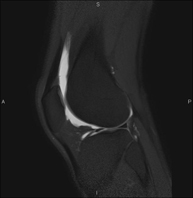

- Knee MRI

Examination to study joint injuries, such as meniscal tears and cruciate ligament tears (only detectable through this test), chondropathy or cartilage wear, and a multitude of other disorders resulting from sports activities and degenerative changes (osteoarthritis). It lasts approximately 18 minutes. It is a radiation-free procedure.